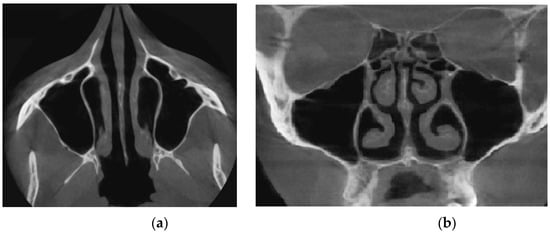

Verification of rhinomanometric data should be performed on the basis of tomographic data of the conditional norm and pathological conditions, which, due to various factors, affect nasal aerodynamics in different ways. Thus, in Figure 12 it is possible to see the characteristic tomographic sections of the nasal cavity at the conditional norm in the axial (Figure 12a) and frontal (Figure 12b) planes.

Figure 13 shows tomographic data of a patient with a curvature of the nasal septum to the left in the middle section, where you can clearly see a large change in configuration in the middle section of the nasal cavity on both axial (Figure 13a) and frontal (Figure 13b) sections.